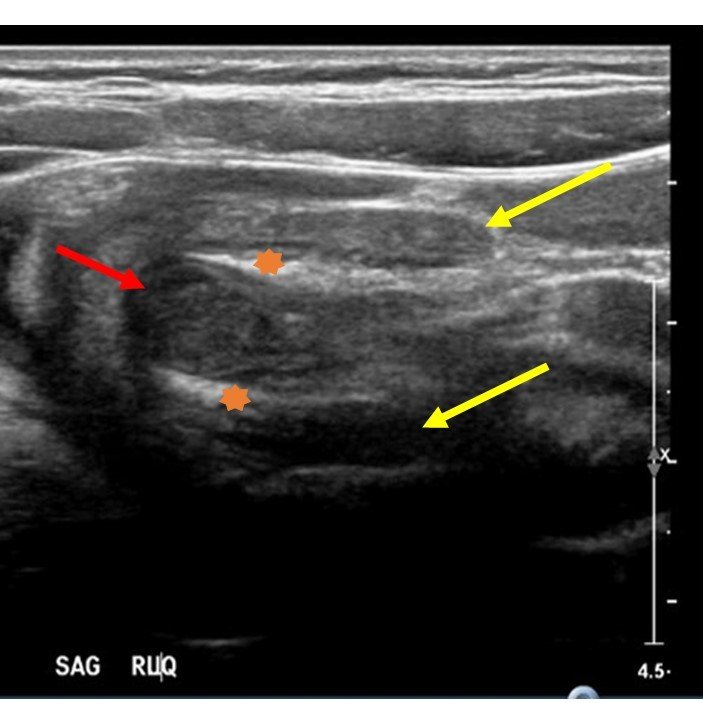

Significant findings:

The patient’s abdominal ultrasound revealed intussusception in the right upper abdominal quadrant. The transverse ultrasound view showed a “doughnut sign” (dashed yellow line), telescoping bowel (yellow arrow), and invaginated hyperechoic mesenteric fat with crescent configuration (dashed orange line). The sagittal ultrasound view demonstrated the intussusception formed by the outer recipient bowel loop (yellow arrows), invaginated hyperechoic mesenteric fat (orange asterisks), and telescoping bowel centrally (red arrow).